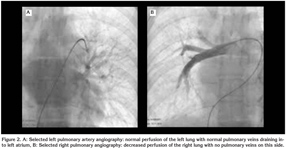

A 20-year-old female college student admitted to our clinic with dsypnea on exertion. She had this complaint for two years. On her past medical history she had pneumonia three years ago. On physical examination respiratory sounds were decreased on right hemithorax and cracles were heard on base of the right lung. Direct chest X-ray was obtained which revealed reduced volume of the right lung with shift of trachea to this side (Figure 1A). Computed tomographic examination of the chest showed decreased volume and interstitial disease pattern on right lung with shift of mediastinal structures to ipsilateral side. Right pulmonary veins were not identified on tomographic scans (Figure 1B). On transthoracic Doppler echocardiographic examination the right pulmonary veins were also could not be visualized. The estimated systolic pulmonary pressure on Doppler examination was normal. The right and left ventricular function were found as normal and interatrial and interventricular septums were intact. To confirm the diagnosis cardiac catheterization and pulmonary angiography were performed. On oxymetric study oxygen saturation was higher on right pulmonary artery than that of the left (99% vs. 89%, respectively). This finding suggested the presence of systemic arterial blood flow to pulmonary arteries on the affected side. On selected left pulmonary artery angiography the perfusion of the left lung was identified to be normal with normal pulmonary veins draining into left atrium (Figure 2A). However on selected right pulmonary angiography decreased perfusion of the right lung was noted and pulmonary veins on this side were not visualized (Figure 2B). Instead prominent intercostal arteries were identified supplying blood to the right lung. The patient was discussed with cardiologists and cardiovascular surgeons and conservative approach was chosen for her. She and her family were informed about this condition and close follow up were scheduled.

Figure 1